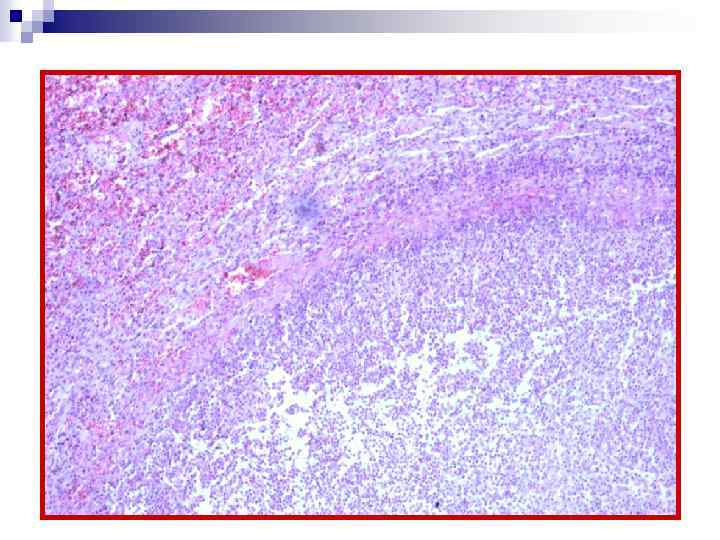

Абсцесс (іріңдік) – шектелген (ошақты) іріңді қабыну; ірің жиналған қуыс қалыптасыруға бейім. Абсцесс дәнекер тіндік қабық түзеді. Ол қабықтың ішкі қабаты капиллярлары көп грануляциялық тіннен (пиогендік мембрана), ал сыртқы қабаты дәнекер тін талшықтарынан (фиброзды қабат) түзіледі. n

Абсцесс (пиогендік мембрана) Абсцесс (пиогенная мембрана)